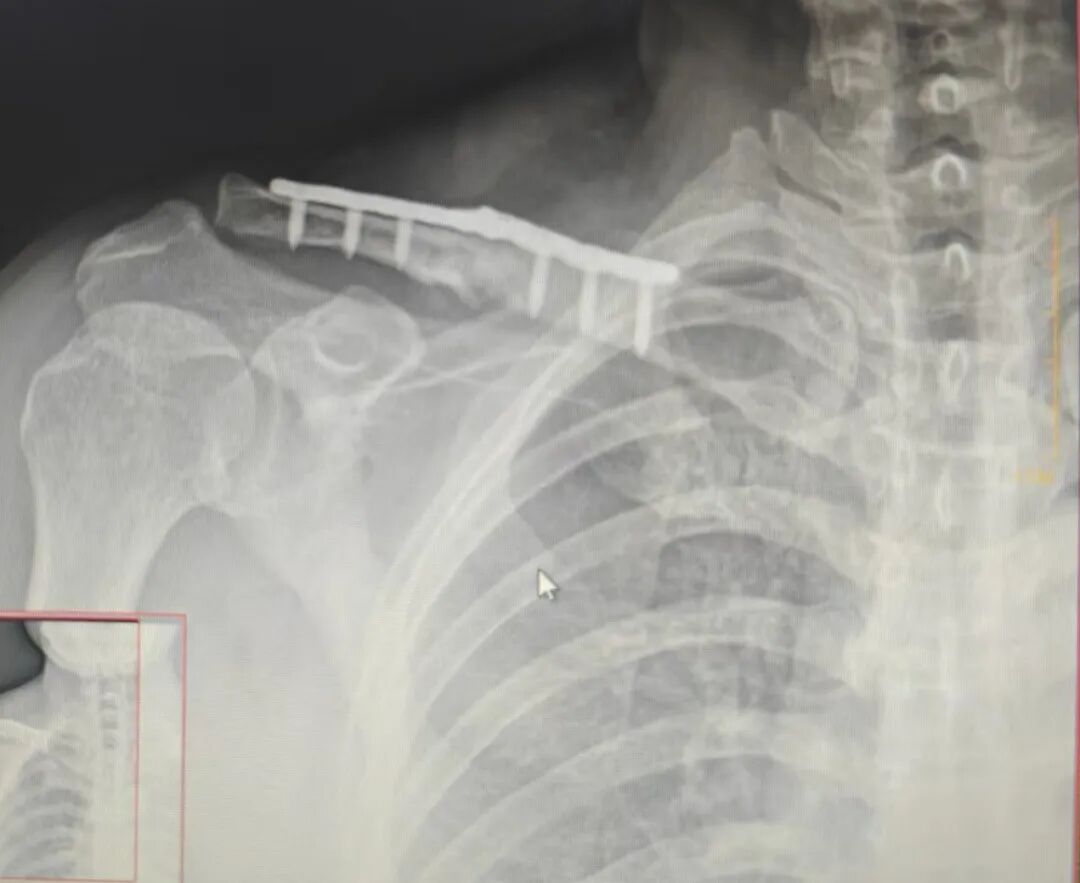

2个月后来复查

长势喜人

骨折愈合良好

断板也复位了